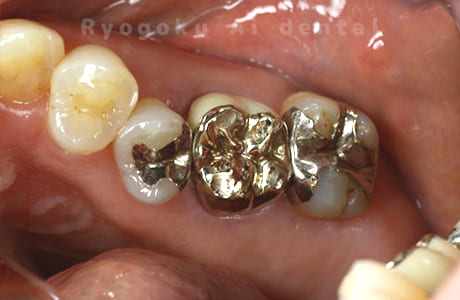

Case07

- 慢性根尖性歯周炎(16・17・15部)

- 治療内容

- マイクロエンド(3歯分)

- 308,000円(3歯分)※被せ物を除く

右上の違和感が取れないとのことで来院された患者さんです。ファイルという器具が歯の根の中で折れていることを説明し、マイクロスコープを使用した根管治療を提案し、治療を行いました。折れたファイルも取り除くことができ、現在の経過は良好です。